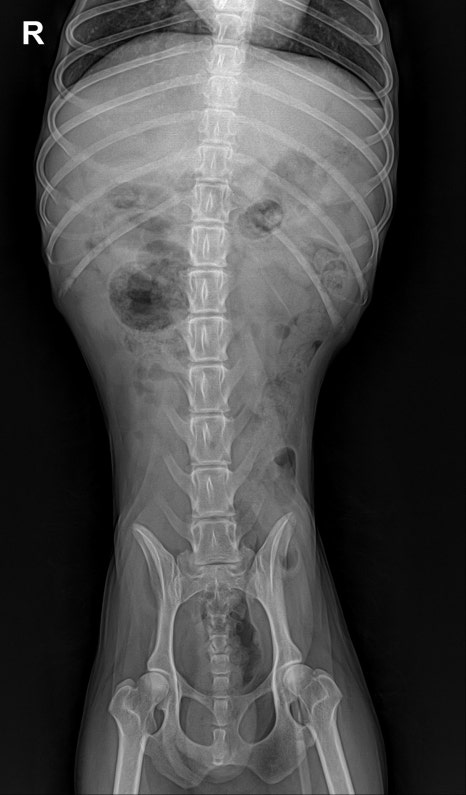

복부 방사선 검사: 이물 없음

- 복부 방사선 검사: 이물 없음